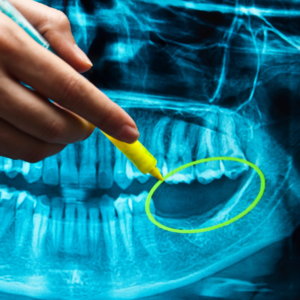

Periapical x-rays focus on one or two teeth, from crown to root. They’re ideal for spotting root infections or abscesses. Panoramic x-rays capture the entire mouth in one image, perfect for wisdom teeth, jaw issues, or detecting cysts. Occlusal x-rays show how teeth align, often used for kids’ bite development.

Dental X-Rays Work

Dental x-rays use energy waves that pass through soft tissues but are blocked by dense structures like teeth and bones. A machine sends a focused beam through your mouth to a sensor or film. Dense areas appear white, while cavities or gaps show darker. The process is quick, painless, and takes seconds. You wear a protective bib and stay still.Jaw Pain After Dental Work, TMJ Locking, Swollen Cheek – Healthhype

Digital x-rays display images instantly on a screen, while older film x-rays need developing. This technology, dating back to 1895, has evolved to be safer and faster. Dentists analyze the images to spot hidden issues, ensuring accurate diagnoses without invasive methods.